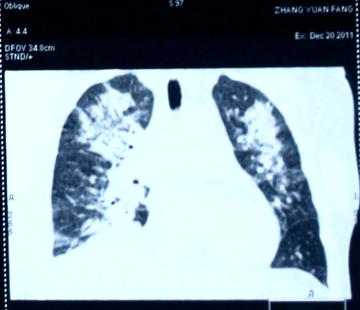

(1)吸入性肺炎的治疗:

入院时的胸部X线片:见图1

图1

第3天的胸部X线片:见图2

图2